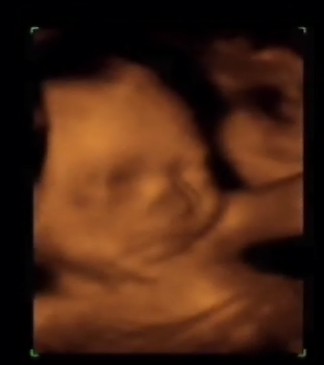

El desarrollo cerebral es evidente, y comienzan a verse "plegamientos" cerebrales denominados circunvoluciones que en el mes anterior apenas existían. Este desarrollo cerebral permite que comience a aprender y memorizar. Desde el punto de vista de la motilidad, esto se traduce en que sus movimientos son cada vez más finos, y comienza ya a ensayar una gran cantidad de gestos y muecas con las que nos deleitará en la ecografía 3D/4D que habitualmente se realiza en el siguiente mes.

Entre las 24 y 31 semanas, es quizás el mejor momento para la realización de ecografías 4D aunque ya han visto que pueden hacerse en cualquier momento. Observen como el feto arrastra su cara sobre la placenta y hace movimientos de succión. ¿Se estará entrenando para la lactancia?